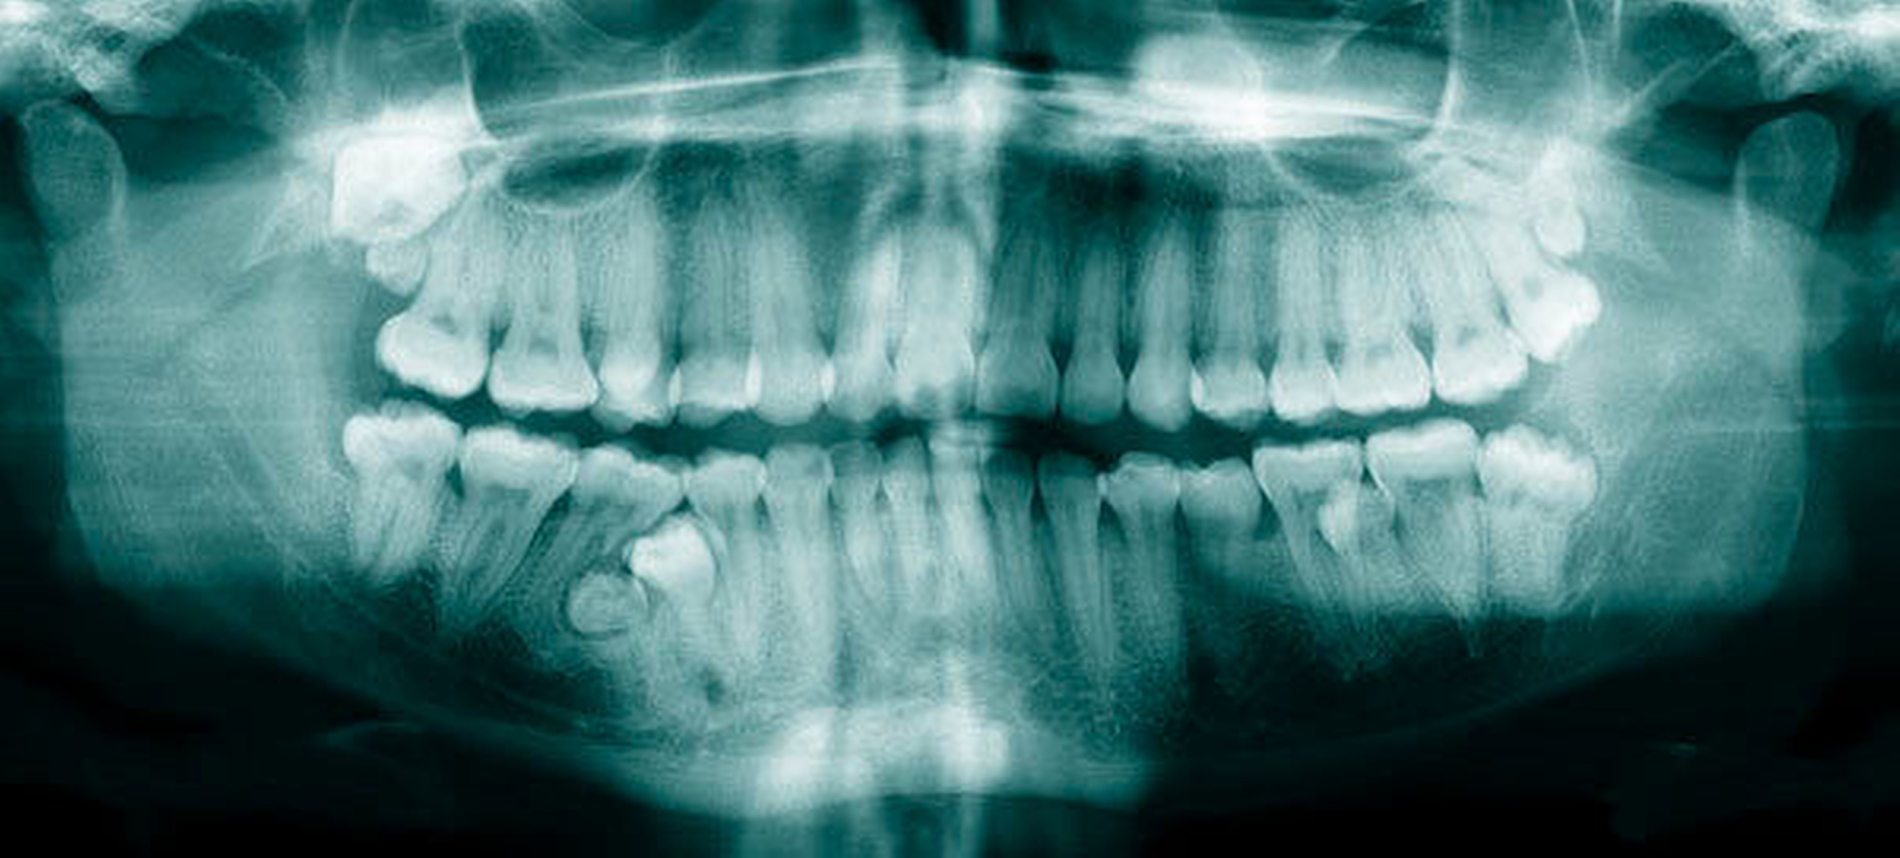

Epidemiologie und ätiologische Faktoren: Überzählige Zähne entwickeln sich zusätzlich zur normalen Dentition. Sie können in der primären oder permanenten Dentition auftreten und in allen Regionen des Ober- oder Unterkiefers vorkommen. Sie werden in der Regel zufällig auf (intraoralen) Röntgenbildern während zahnärztlichen Kontrolluntersuchungen entdeckt. Ein erstes Anzeichen eines überzähligen Zahnes kann auch eine Verzögerung des normalen Zahndurchbruchs sein, was in der Folge zu einer klinisch-radiologischen Abklärung der möglichen Ursache führt. In der Literatur finden sich einige Untersuchungen mit teils unterschiedlichen Daten zur Prävalenz, zum Geschlechterverhältnis oder auch zur Häufigkeit der verschiedenen morphologischen Typen. Dies lässt sich unter anderem dadurch erklären, dass nicht alle Untersuchungen epidemiologische Studien sind, sondern nicht selten auf ausgewählten Populationen basieren, wie beispielsweise auf Überweisungen an Fachkliniken mit Verdacht auf überzählige Zähne, Patienten einer Schulzahnklinik und mehr. Außerdem gibt es auch geografische Unterschiede, die auf den variablen ethnischen Hintergrund der untersuchten Population hindeuten.

Die Prävalenz überzähliger Zähne wird im Bereich von 0,07 Prozent bis 0,6 Prozent für das Milchgebiss [Luten, 1967; Ravn, 1971; Järvinen Lehtinen, 1981; Magnússon 1984; Skrinjari Barac-Furtinovi, 1991; Yonezu et al., 1997; Chen et al., 2010] und von 0,3 Prozent bis 3,2 Prozent für die bleibenden Zähne [Luten, 1967; Bäckman Wahlin, 2001; Salcido-García et al., 2004; Leco Berrocal et al., 2007; Gündüz et al., 2008; Yagüe-García et al., 2009; Schmuckli et al., 2010; Fardi et al., 2011] angegeben. Die Mehrheit der überzähligen Zähne im Milchgebiss sind seitliche Schneidezähne im Oberkiefer, die meist mit einer normalen Morphologie und Lage durchbrechen (Abbildungen 1 bis 3) [Luten, 1967; Humerfeld et al., 1985; Garvey et al., 1999; Ferrés-Padró et al., 2009]. Der oft ungestörte Durchbruch und das Ausbleiben von Symptomen führen dazu, dass überzählige Zähne in der Milchdentition oft gar nicht diagnostiziert werden, und dies wird auch als Erklärung für die unterschiedlichen Prävalenzen überzähliger Zähne im Milch- und bleibendem Gebiss angeführt [Wang Fan, 2011]. Überzählige Zähne sind häufiger bei Männern als bei Frauen, wobei über ein Verhältnis von 1,18:1 bis 4,5:1 berichtet wird [Rajab Hamdan, 2002; Fernández Montenegro et al., 2006; Gündüz et al., 2008; Wang Fan, 2011]. In der Schweiz publizierten von Arx (1990) und Schmuckli und Mitarbeiter (2010) Geschlechterverhältnisse von 2,6:1, beziehungsweise 2,75:1. In einer aktuellen Arbeit von Mossaz und Mitarbeiter (2014) von Patienten aus dem Raum Bern lag dieses Verhältnis etwas ausgeglichener bei 1,61 zu 1.

Überzählige Zähne werden nach ihrer Lage im Zahnbogen und auch aufgrund ihrer Morphologie eingeteilt. Basierend auf der Lage unterscheidet man bei überzähligen Zähnen zwischen Mesiodens (Oberkiefer median), zwischen den zentralen Inzisiven (Abbildungen 5 und 6), einem zusätzlichen Schneidezahn (zentral oder lateral), Eckzahn, Prämolar (Abbildung 7), Paramolar und Distomolar (Abbildungen 8). Mesiodentes werden am häufigsten dia- gnostiziert, wobei Prozentsätze zwischen 38,8 Prozent bis 86,3 Prozent der überzähligen Zähne in der Literatur zu finden sind [Salcido-García et al., 2004/38,8 Prozent, Fernández Montenegro et al., 2006 /46.9 Prozent; Mossaz et al., 2014/48.5 Prozent; Ferrés-Padró et al., 2009/53.2 Prozent; Schmuckli et al., 2010/75 Prozent; Rajab Hamdan 2002/83.2 Prozent; Liu et al., 2007/86.3 Prozent]. Überzählige Prämolaren und seitliche Schneidezähne sind die zweithäufigste Gruppe der überzähligen Zähne. Überzählige Eckzähne, Paramolaren und Distomolaren dagegen gelten als eher selten [Rajab Hamdan, 2002; Salcido- García et al., 2004; Liu et al., 2007; Ferrés-Padró et al., 2009; Schmuckli et al., 2010; Mossaz et al., 2014]. Einzig eine Spanische Gruppe [Fernández Montenegro et. al., 2006] berichtete, dass Paramolaren und Distomolaren insgesamt relativ häufig seien (18 Prozent, beziehungsweise 5,6 Prozent). Überzählige Zähne kommen im Ober- und Unterkiefer vor, wobei sich überzählige Schneidezähne in der Regel im Oberkiefer, überzählige Prämolaren sich dagegen eher im Unterkiefer befinden [Fernández Montenegro et al., 2006; Ferrés-Padró et al., 2009; Mossaz et al., 2014]. Überzählige Molaren wiederum treten normalerweise im Oberkiefer auf [Cassetta et al., 2014; Kaya et al., 2014].